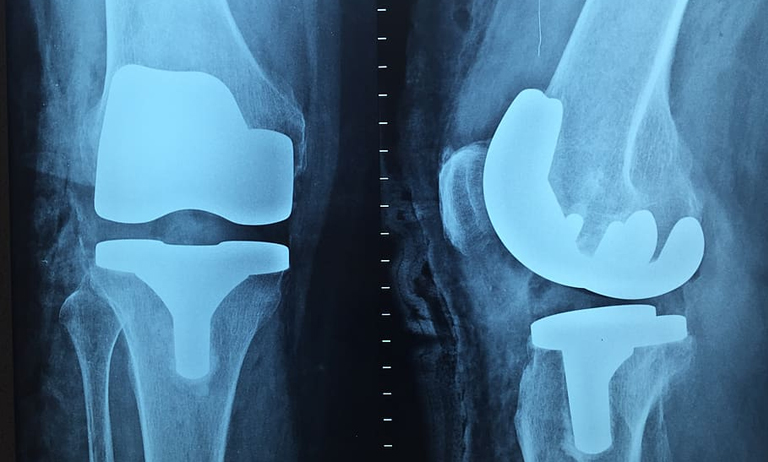

醫(yī)療工(gōng)程

适用(yòng)于醫(yī)療工(gōng)程,如人工(gōng)關節、手術器械等高(gāo)精度加工(gōng),符合各項認證要求。